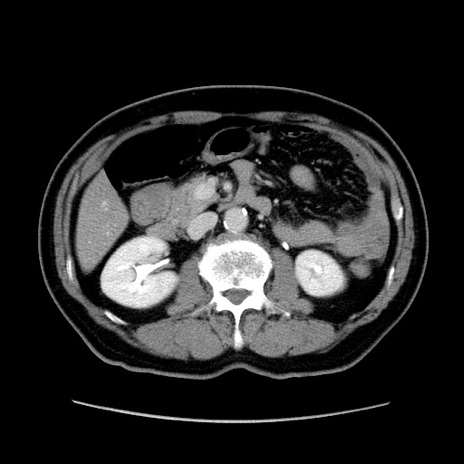

症例34(横断像)

【症例】60歳代 男性

【主訴】右鼠径部膨隆

【現病歴】1年程前より右鼠径部膨隆あり。自己にて還納可能だったため放置していた。3時間前より右鼠径部の脱出を認め、還納困難となり受診。

【身体所見】右鼠径部に小児頭大の膨隆あり。弾性硬であり、用手還納は困難。左鼠径部にも膨隆を認める。脱出はなし。